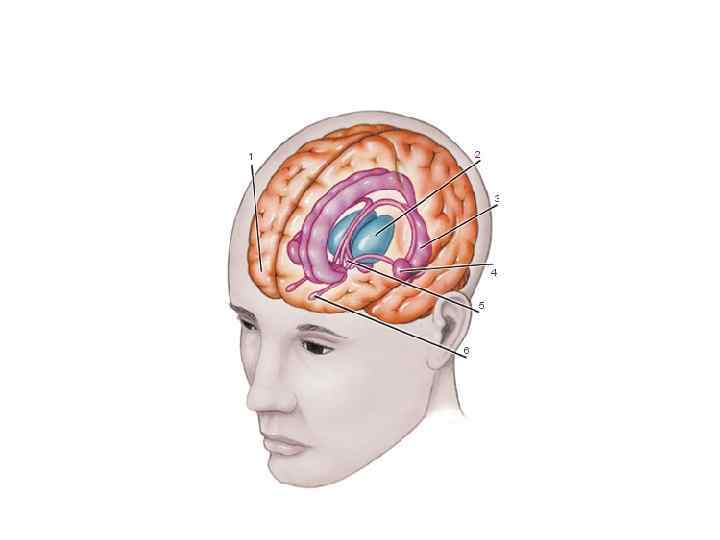

Общие план строения эндокринной системы 1. Гипоталамус – отдел промежуточного мозга, высший центр регуляции эндокринных функций. 2. Гипофиз – центральная железа внутренней секреции. 3. Периферические железы: эпифиз, щитовидная, паращитовидные, поджелудочная, половые железы, надпочечники.

Общие план строения эндокринной системы 1. Гипоталамус – отдел промежуточного мозга, высший центр регуляции эндокринных функций. 2. Гипофиз – центральная железа внутренней секреции. 3. Периферические железы: эпифиз, щитовидная, паращитовидные, поджелудочная, половые железы, надпочечники.

Верхний отдел мозгового ствола – ПРОМЕЖУТОЧНЫЙ МОЗГ: Состав: – ТАЛАМУС (ворота в кору) – ГИПОТАЛАМУС (регуляция эндокринных функций и инстинктивного поведения)

Верхний отдел мозгового ствола – ПРОМЕЖУТОЧНЫЙ МОЗГ: Состав: – ТАЛАМУС (ворота в кору) – ГИПОТАЛАМУС (регуляция эндокринных функций и инстинктивного поведения)